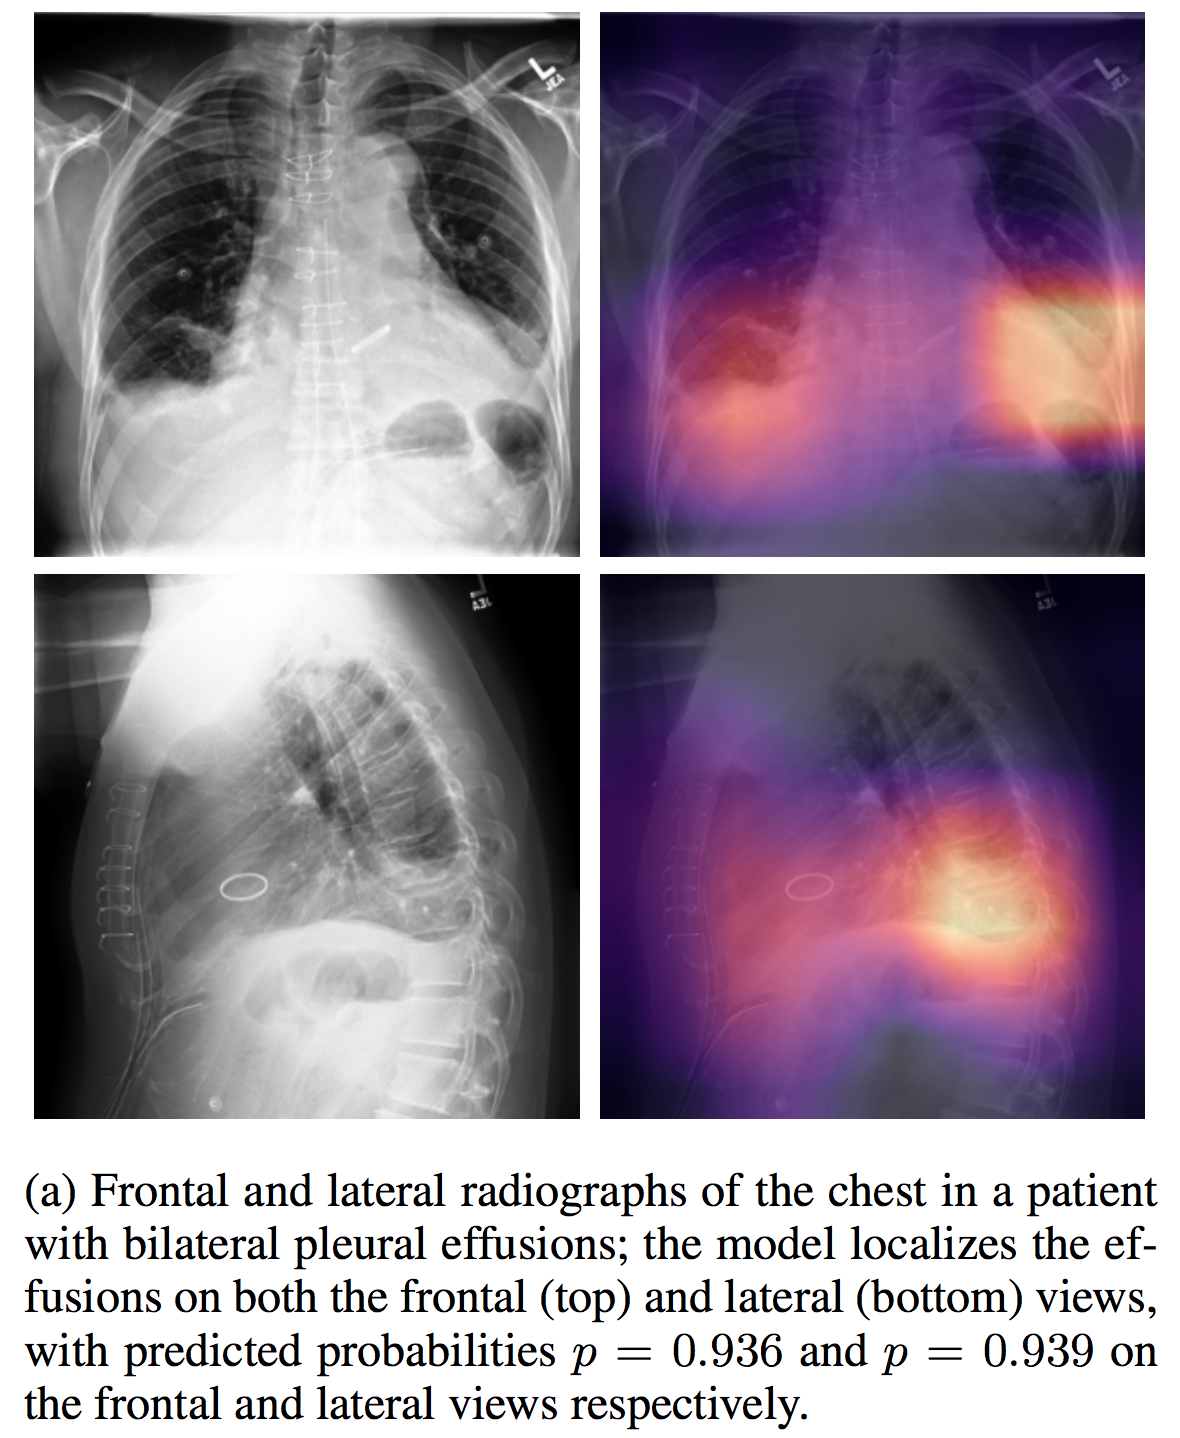

CheXpert

| CheXpert | Other |

介绍论文: CheXpert: A Large Chest Radiograph Dataset with Uncertainty Labels and Expert Comparison

NIHChest Xray

| NIHChest Xray | 14种肺部疾病/部分病灶位置 | 分类/检测 | CXR | 112,120 | csv | png | CC0: Public Domain |

介绍论文: ChestX-ray8: Hospital-scale Chest X-ray Database and Benchmarks on Weakly-Supervised Classification and Localization of Common Thorax Diseases